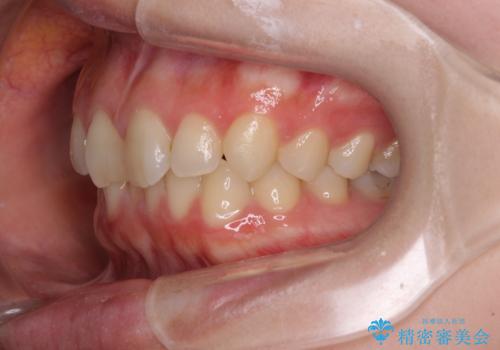

- 近々転勤の予定があるが、早めにインビザラインによる矯正治療を始めたいとのことで来院された患者様です。

上下ともにデコボコの程度は著しいものではなく、インビザラインで十分に対応可能な歯列不正でした。

後戻りによりスペースができてしまうことを避ける目的で、IPR(歯と歯の間を削る)を極力用いない矯正治療を行うこととしました。

インビザラインであれば来院間隔が多少長くなってもワイヤー矯正ほど問題とならないため、遠方からの通院であっても中断や転院せずに治療を行うことができます。